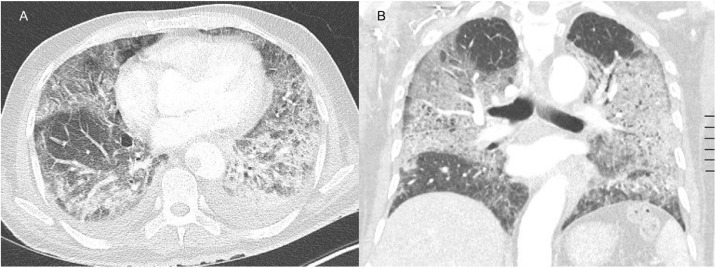

Computed tomography angiography (CTA) of the thorax showed ground glass opacities in the five lobes, but no signs of pulmonary embolism (Figure 2). The patient was treated with dexamethasone, a prophylactic dose of low molecular weight heparin (LMWH), high flow oxygen therapy, and a single infusion of tocilizumab within a clinical trial (Maes et al., 2020).

Figure 2.

Axial (A) and coronal (B) contrast-enhanced CT image in pulmonary window showing extensive ground glass opacities.